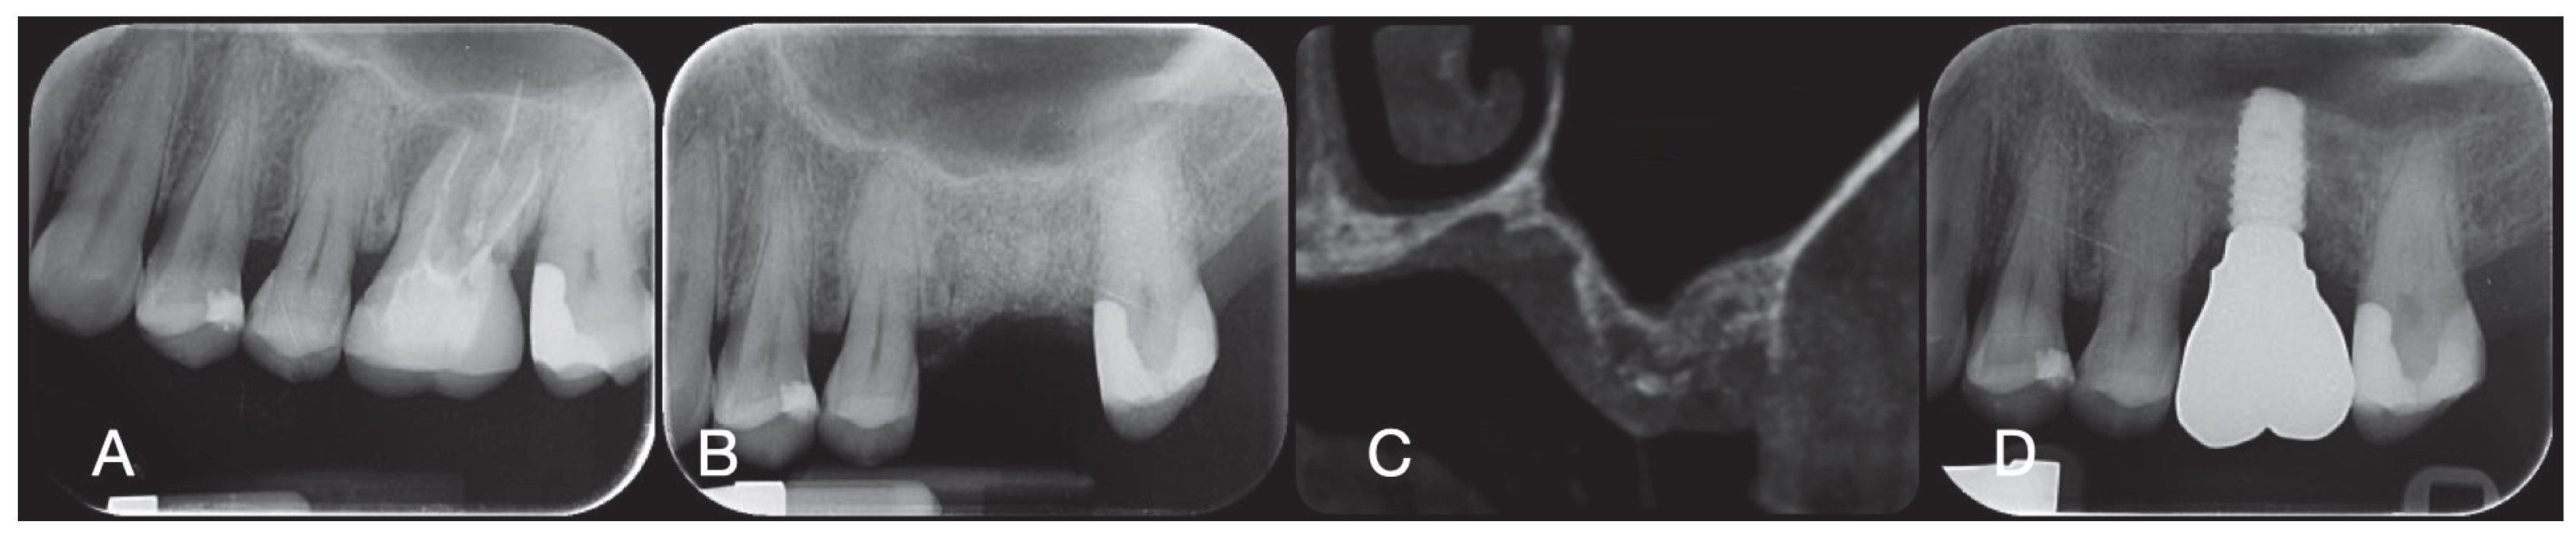

2.1. Socket Preservation Procedure

2.2. Post-Surgical Instructions and Prosthetic Phase After Socket Preservation

2.3. Biopsy Retrieval

3.1. Clinical Outcomes